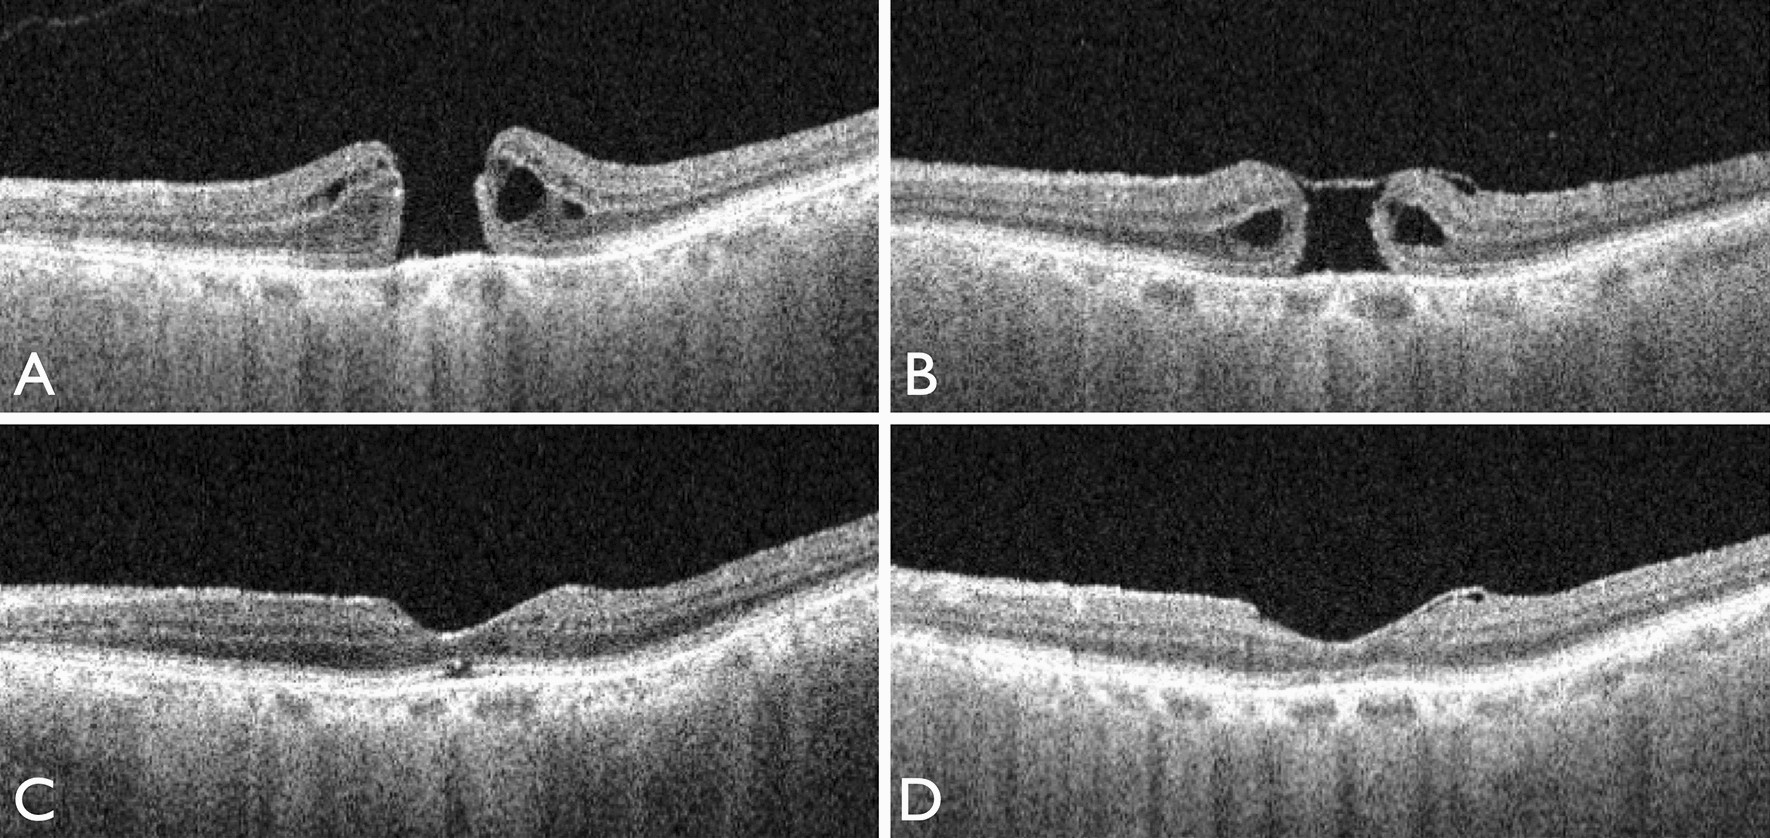

contractility of temporal inverted internal limiting membrane flap after vitrectomy for macular hole scientific reports